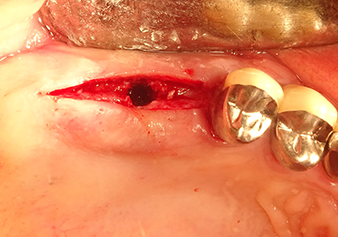

Implant bed preparation and augmentation

Following an intermediate check (Fig. 4) a further preparation step was performed (Fig. 5). Afterwards, the hydraulic Z35P instrument was used to lift the membrane to the desired position (Fig. 6 and 7). This was followed by further piezosurgical preparation of the implant bed, concluded with a rotary bur and shoulder milling cutter up to the implant diameter of 4.8 mm. Before the implant was inserted, the augmentation material (particle size approx. 0.8-1.6 mm) was introduced underneath the Schneiderian membrane (Fig. 8).